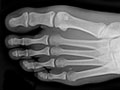

Extremity X-Ray

Test Overview

An extremity X-ray is a picture of your hand, wrist, arm, foot, ankle, knee, hip, or leg. It is done to see whether a bone has been fractured or a joint dislocated. It is also used to check for an injury or damage from conditions such as an infection, arthritis, bone growths (tumours), or other bone diseases, such as osteoporosis.